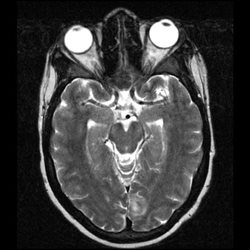

27 yo male with treated ALL, now neutropenic. He presented with fever, and systemic infectious symptoms. MR